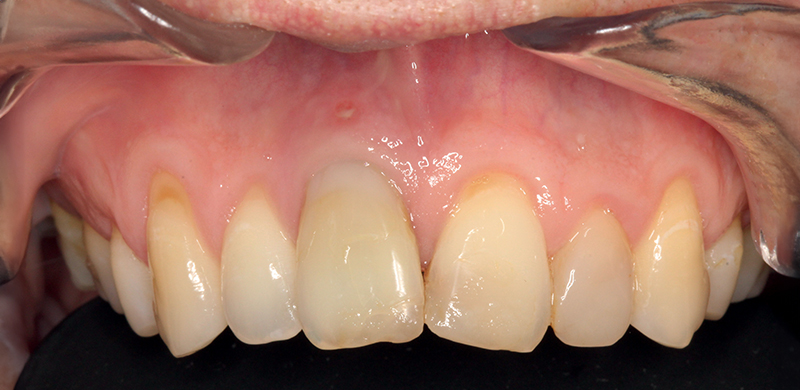

Fig. 10 (caso 2) - Vista frontale dopo 3 mesi dall'inserimento dell'impianto

Caso 2: Una paziente di 33 anni si presentava con corona clinica del dente 11 scolorita, associata ad una linea del sorriso alta, che rappresentava una sfida per il risultato estetico. Il dente era associato a riassorbimento apicale, cisti e sintomi dolorosi. Veniva estratto e la paziente riceveva un impianto SDS. L'intervento seguiva scrupolosamente il protocollo di perforazione ossea suggerito dal produttore, e l'intervento mini-invasivo manteneva intatte la parete buccale dell'alveolo dentale. La competenza del chirurgo si rivelava fondamentale per ottenere un risultato estetico favorevole, fin dai primi passi. Lo spazio tra l'impianto e la parete vestibolare (circa 0,5-1 mm) veniva riempito con matrici PRF, per stimolare la formazione di nuovo osso. In questo caso non era necessaria la sutura. Dopo 3 mesi l’impianto era preparato e la paziente riceveva la corona definitiva. La paziente era soddisfatta del trattamento (Fig. 3-10).